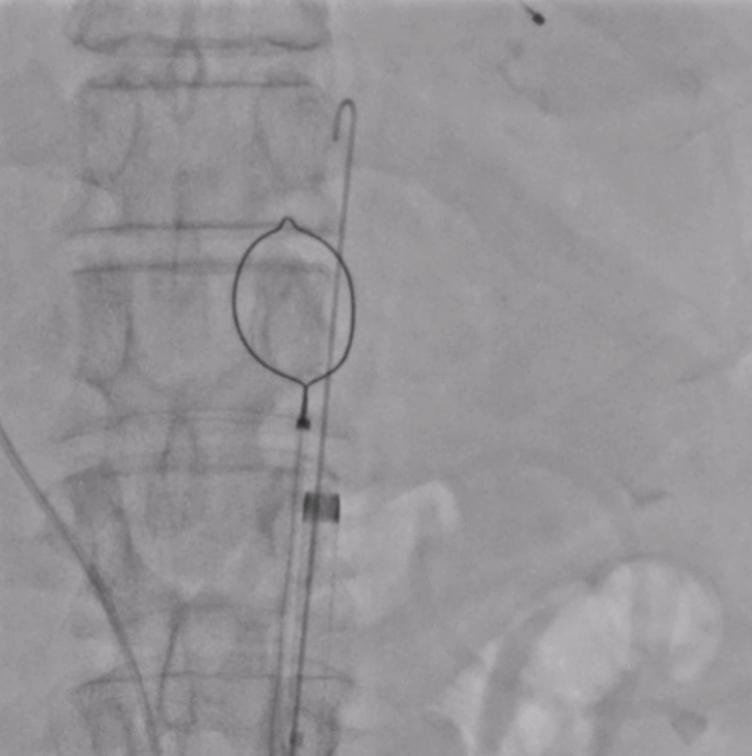

The patient was planned for transfemoral TAVI. Both left and right femoral arteries were punctured under ultrasound guidance. A temporary pacemaker (TPA) was placed in the right ventricle via the left femoral artery, and the right femoral artery sheath was upgraded to the 14Fr sheath. Selective left coronary angiography revealed normal coronaries. Through the right femoral artery, a snare was deployed in the abdominal aorta. The native bicuspid aortic valve was crossed with an Lunderquist wire, which was advanced into the left ventricle. Using pigtain, angiographic gradient was measured, showing severe aortic stenosis. Predilatation was performed using a 20 mm Z-MED balloon with satisfactory results. The TAVI valve, a self-expanding valve, was advanced across the native valve with the aid of the snare and positioned accurately in the cusp-overlap view. Under rapid pacing, the valve was deployed up to 80%, and after confirming satisfactory depth, full deployment was completed in the coplanar view. Final angiographic assessment showed no paravalvular leak (PVL) or aortic regurgitation (AR), with valve depth of 4–5 mm at the NCC and 6–7 mm at the LCC. Femoral closure was performed successfully without vascular complications.